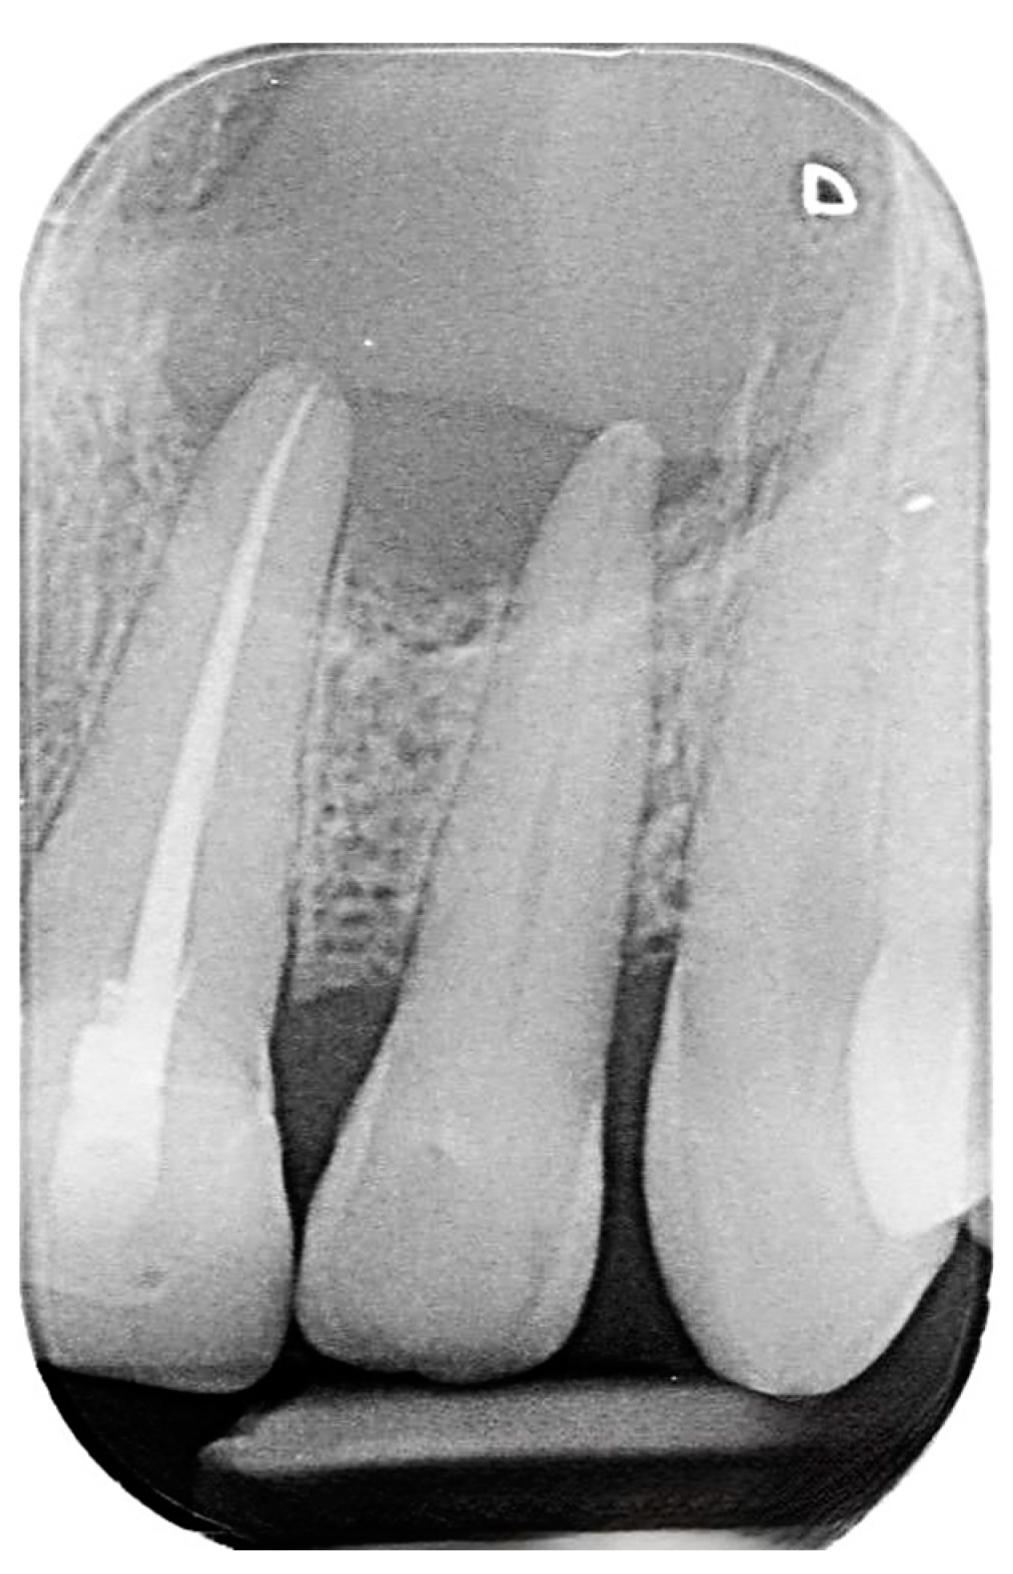

2. Case Presentation

2.1. Chief Complaints History and Clinical Findings

2.2. Delivery of Treatment